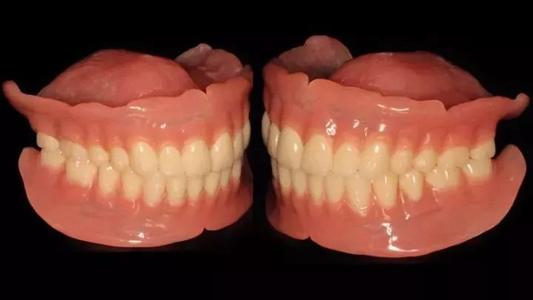

2、活動義齒

適合于:多顆牙連續(xù)缺失且一側(cè)沒有健康牙齒的情況,或者是半口牙缺失甚至全口牙缺失的患者。

優(yōu)點:可以很快修復(fù)缺失牙齒(拔牙后2個月就可以修復(fù)),對牙槽骨及剩余牙齒的健康程度要求不高,費(fèi)用相對較低。

缺點:需要每天飯后及睡覺前取下來清洗,恢復(fù)的咀嚼功能較少,對剩余的牙齒有直接或者間接的損傷,一般3-5年就得更換。